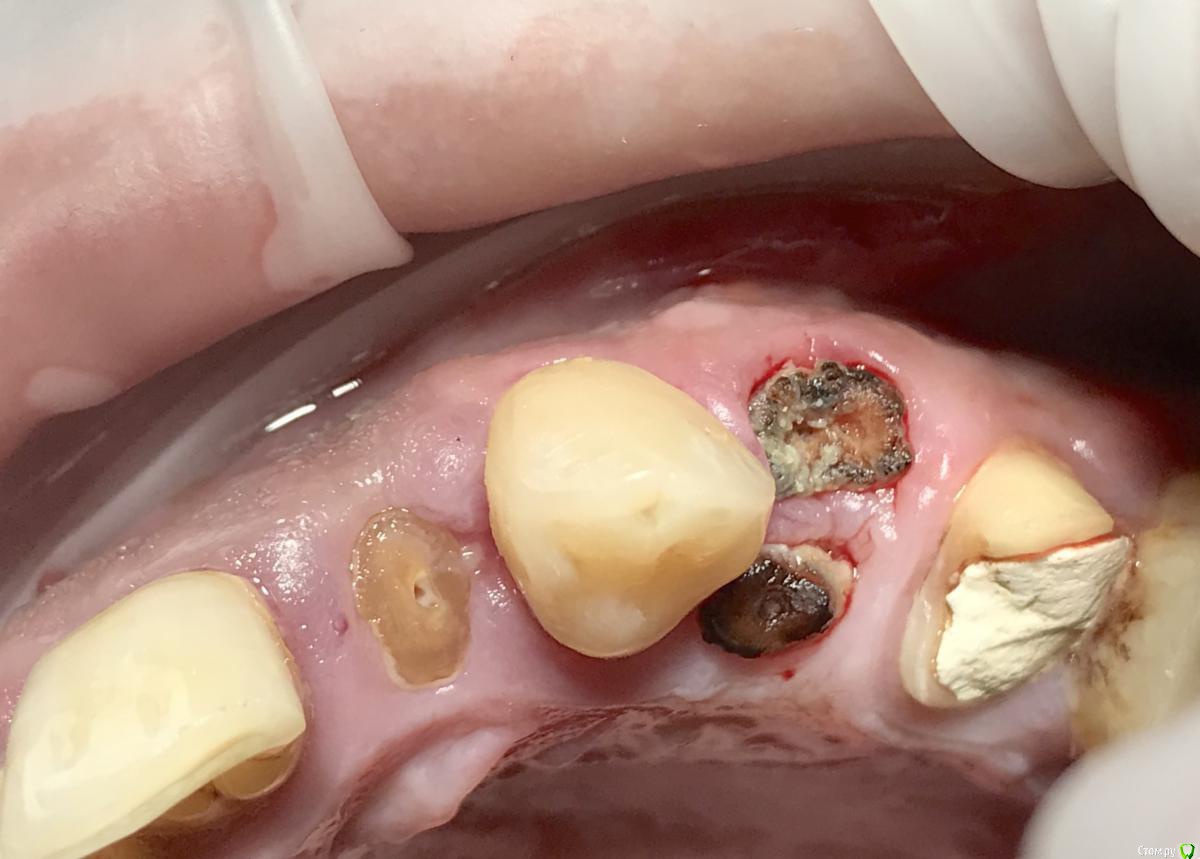

колесников Опубликовано 10 апреля, 2018 Поделиться Опубликовано 10 апреля, 2018 (изменено) С Вашего позволения оставлю это здесь,чтобы темы не плодить. Были проблемные зубы 22,24 с очагами деструкции в периапикальных. Решил удалять с консервацией. Чтобы не портить маргинальную слизистую разрезами и швами ,использовал метод Номаера. На момент съемки : 22ой-неделя после удаления. Закрывал кофердамом. Течение безсимптомное. Изменено 10 апреля, 2018 пользователем колесников 4 Ссылка на комментарий

Bier Опубликовано 10 апреля, 2018 Автор Поделиться Опубликовано 10 апреля, 2018 Недоконца понял тонкости. Вы укоротили корни по высоте, залили выпеленный канал и всё? Или длину сохранили? Вроде на видео корень вдоль пилили? Поясните пожалуйста. Принцип в общем понятен. И по прошествию 3 месяцев корень удаляется или как?из премоляра я сделал шайбу из цервикальной части и вставил в правильном положении. А из моляра я взял дистальный корень, укоротил, высверлил канал, залил композитом и положил боком в лунку. Ссылка на комментарий

Bier Опубликовано 10 апреля, 2018 Автор Поделиться Опубликовано 10 апреля, 2018 С Вашего позволения оставлю это здесь,чтобы темы не плодить. Были проблемные зубы 22,24 с очагами деструкции в периапикальных. Решил удалять с консервацией. Чтобы не портить маргинальную слизистую разрезами и швами ,использовал метод Номаера. На момент съемки : 22ой-неделя после удаления. Закрывал кофердамом. Течение безсимптомное.нужно обязательно канал санировать. И запечатать композитом. Я использую реликс т.к он самопротравливающий и самоадгезивный, меньше мороки и меньше риск повредить связку.У меня в работе практически точно такой же случай. С премоляром, но гнилушки я выбросил и подобрал фрагмент от другого зуба для этой лунки. 1 Ссылка на комментарий